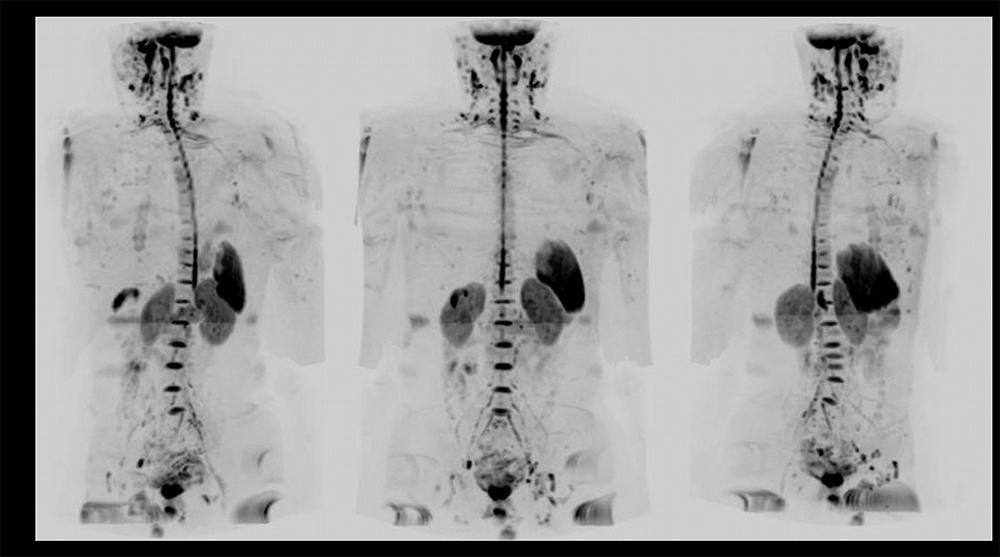

Case3 呼吸器内科:肺癌の骨転移検索目的

70代、男性。肺癌に対して放射線化学療法後、腰痛出現するも単純CTでは原因を特定できず、WBDWIを施行した。WBDWI MIP(①)では、頸椎、胸椎、腰椎、鎖骨、骨盤骨、大腿骨など多発骨転移と肝転移も認められる。②~④の矢状断像では、WBDWI MIP(①)で椎体に重なっていた棘突起の転移、CT(⑤⑨)では描出困難な腰椎、仙骨、腸骨転移(➞)がMRI(⑦⑩)では明瞭に描出されている。まさに骨梁間型骨転移の典型例である。単純CTでは描出されていない肝転移(➞)においてもDWI(⑦)、T2WI(⑧)では明瞭に描出されている(図12)。依頼医からは肺癌は骨梁間型骨転移が多く認められるため、肺癌の骨転移検索にWBDWIは非常に有用であると評価が得られた。

Architect_Okazakishimin02_15.png図12 肺癌の骨転移検索目的